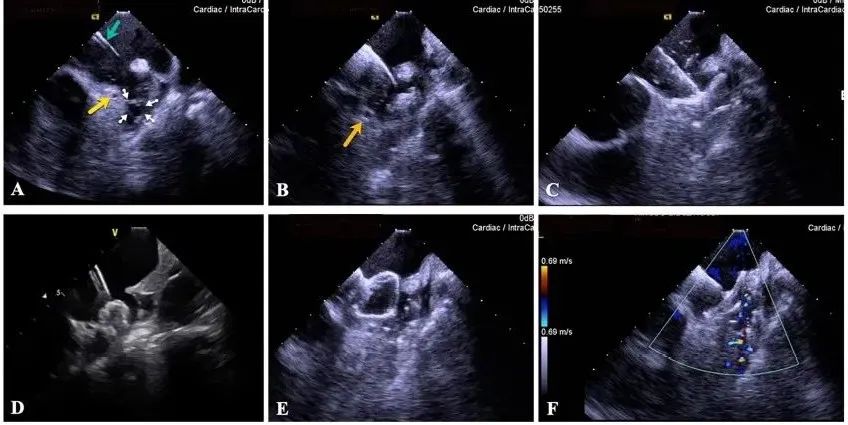

一種與心導(dǎo)管檢查相結(jié)合的超聲心動圖診斷新興技術(shù),通過將超聲探頭置于心腔內(nèi)部,發(fā)射并接收超聲信號,來精確獲取心臟解剖結(jié)構(gòu)、心臟血流動力學(xué)等信息的實(shí)時成像。與其他影像技術(shù)相比,ICE技術(shù)具有操作簡單、無輻射、安全性高、手術(shù)效率高、實(shí)用等優(yōu)勢,ICE在很大程度上有望取代經(jīng)食道超聲心動圖(TEE),成為電生理和結(jié)構(gòu)性心臟病領(lǐng)域的理想成像方式。

目前ICE技術(shù)已被應(yīng)用于左心耳封堵、房顫射頻消融、二尖瓣成形、房間隔缺損封堵等多種心臟介入手術(shù),應(yīng)用場景主要圍繞心臟電生理、結(jié)構(gòu)性心臟病等領(lǐng)域,目前以電生理應(yīng)用為主。數(shù)據(jù)顯示,我國結(jié)構(gòu)性心臟病介入器械市場規(guī)模已從2017年的4億元增長至2021年的20億元,年復(fù)合增長率達(dá)48.3%;預(yù)計到2025年,該市場規(guī)模將達(dá)到104億元,可以預(yù)見ICE市場規(guī)模也將同步高速增長,未來市場發(fā)展空間廣闊。

心腔內(nèi)超聲(ICE)技術(shù)壁壘極高,國內(nèi)主要廠商核心部件仍舊為進(jìn)口,集成了超聲和圖像處理最前端技術(shù),包括超聲探頭、線纜、軟件成像算法等,是當(dāng)前內(nèi)窺超聲方向最具挑戰(zhàn)的領(lǐng)域。ICE的應(yīng)用經(jīng)歷了2D平面成像、3D三維立體成像、以及4D的實(shí)時三維立體成像階段。